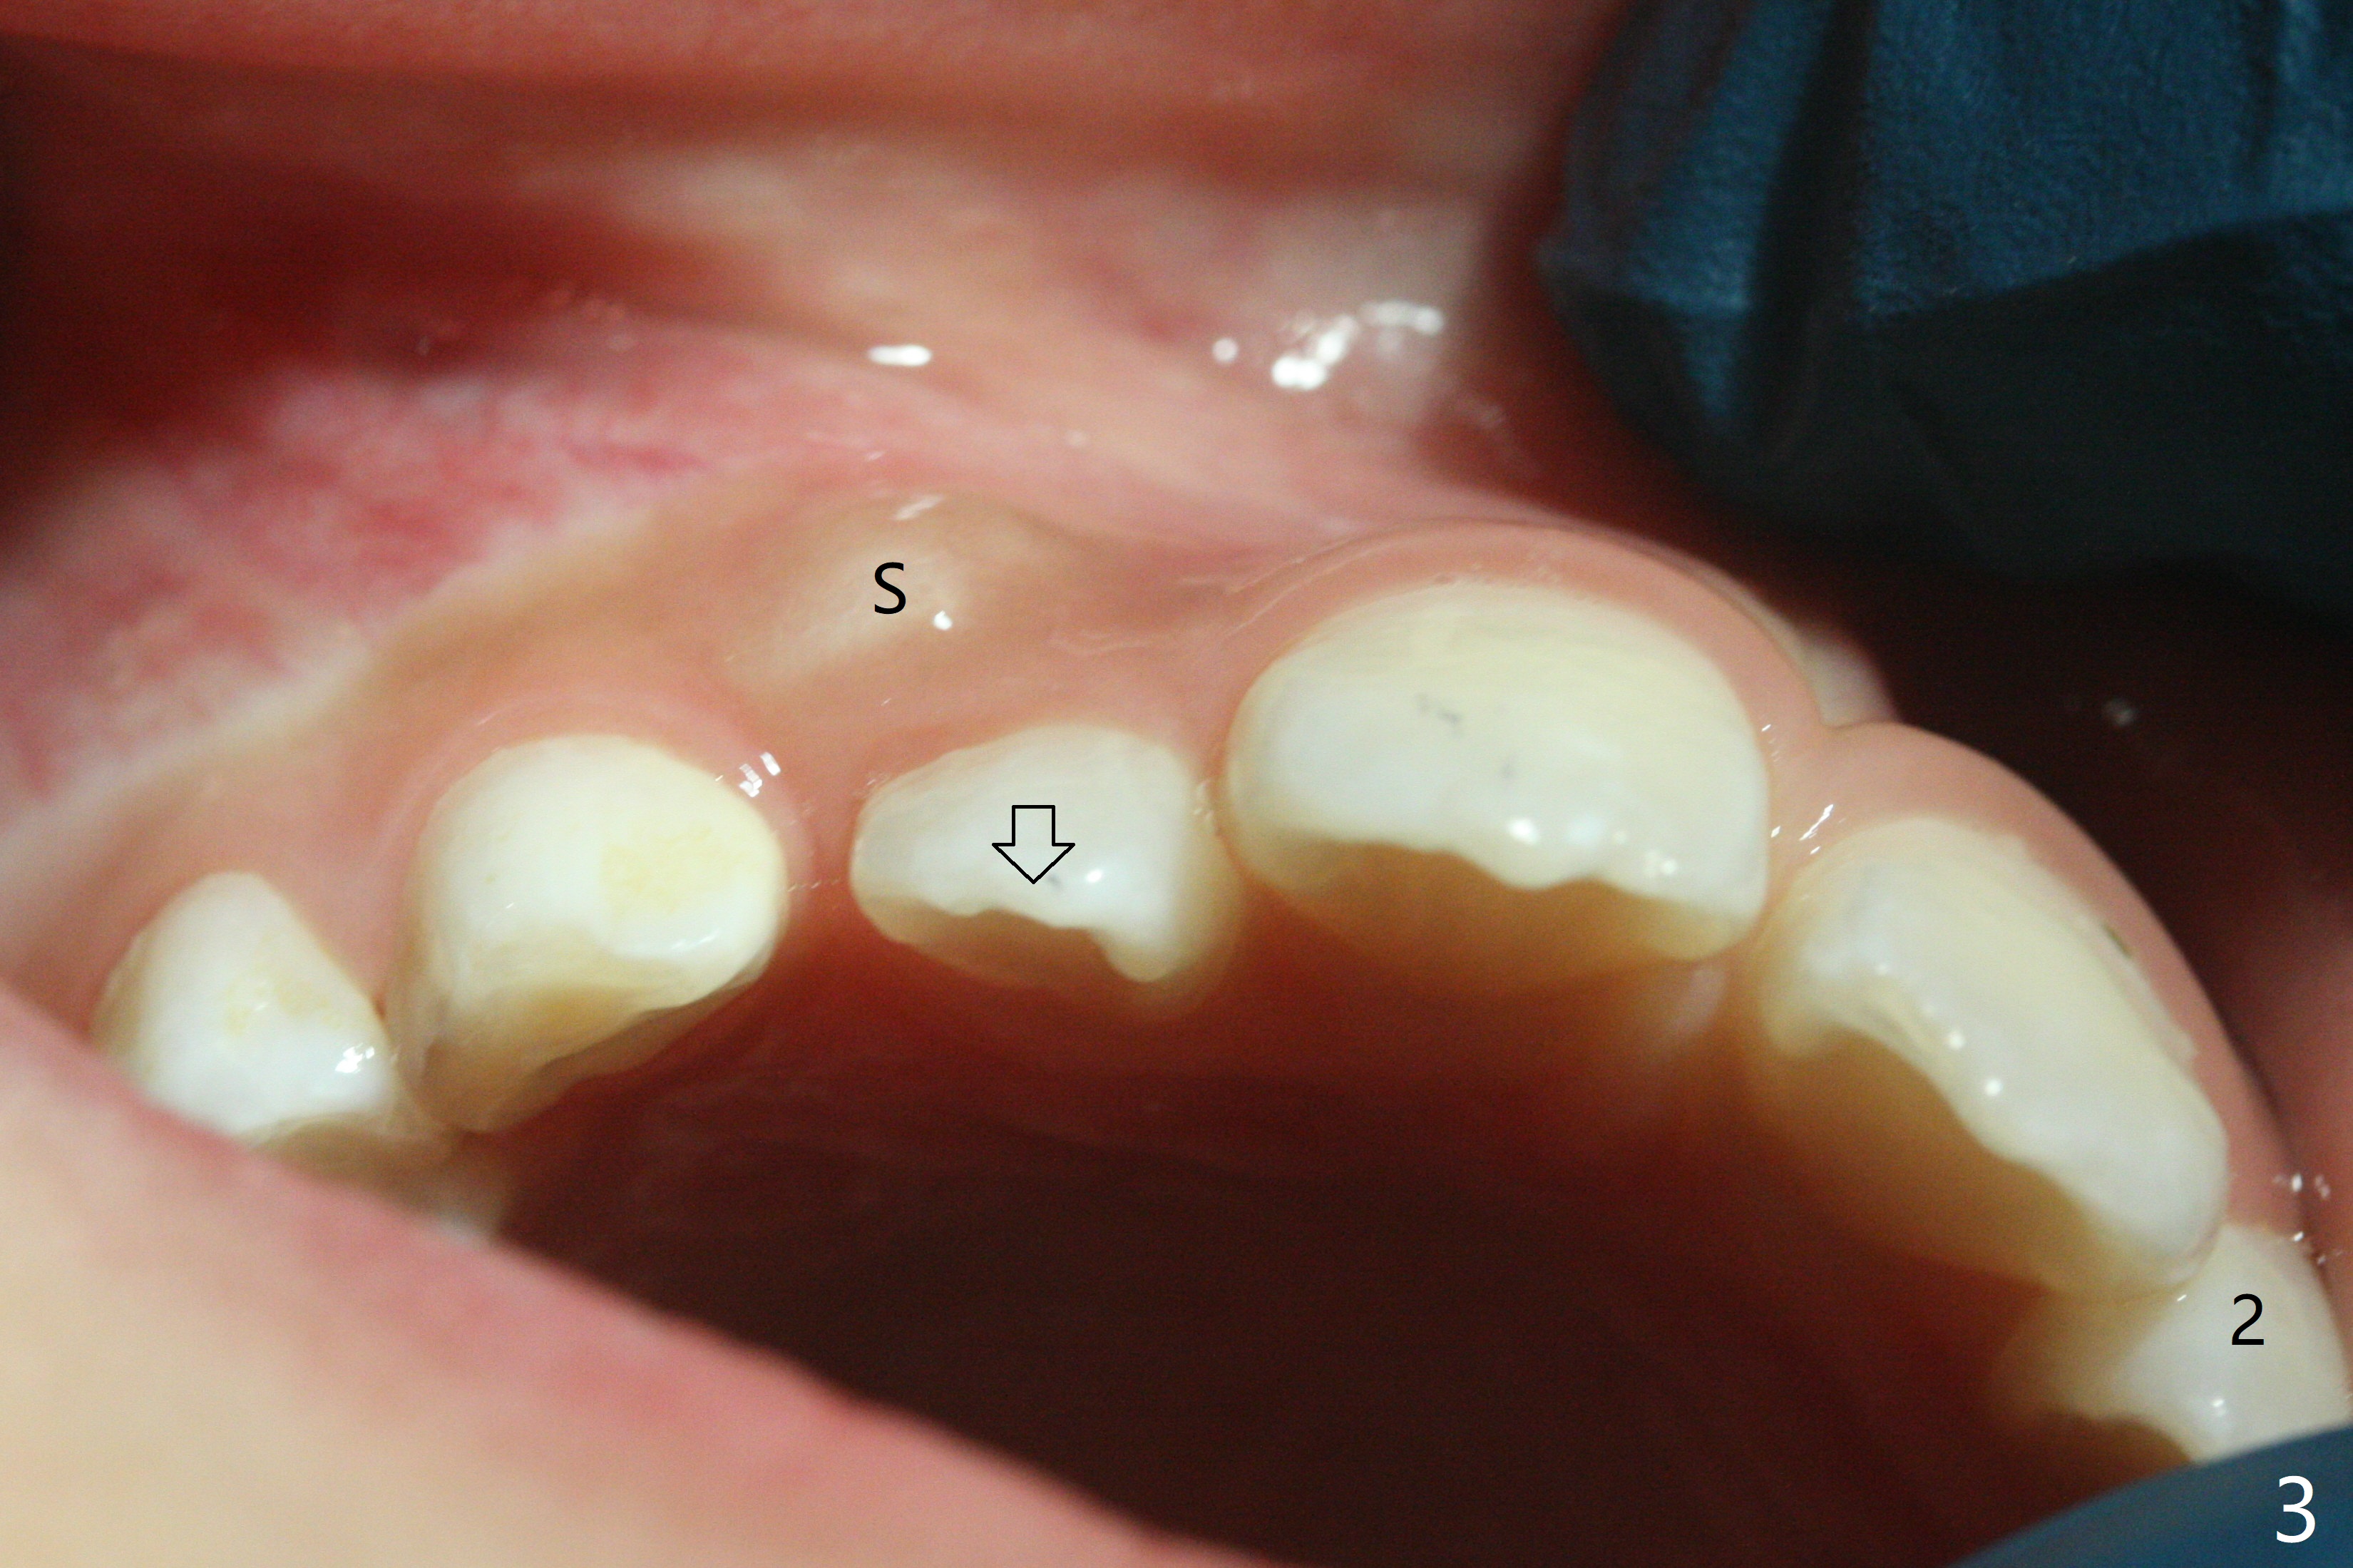

A 6-year-old woman presents to office for limited exam for caries (Fig.1). What was neglected is a super-numerary tooth (S) between UR2 and 3. One year later, the extra tooth appears to be erupting (Fig.2) and linguali-zing UR2 (Fig.3 arrow). PA shows that the extra tooth looks like a lateral (Fig.4). CT will be taken to decide which tooth needs for extrac-tion. The super-numerary tooth (S) blocks UR3 descent, as compared to that of UL3 (Fig.5). The super-numerary tooth with an abnormal cingulum (Fig.6 *) and dens in dente (Fig.6 ^) should be extracted.